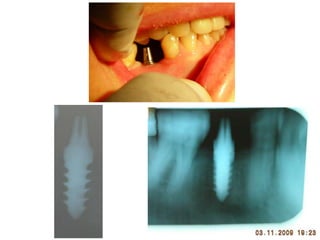

Dogmar Dasgupta,March,2009

Immediately after operation

On 11th.March,2009.

2

9

April,2012